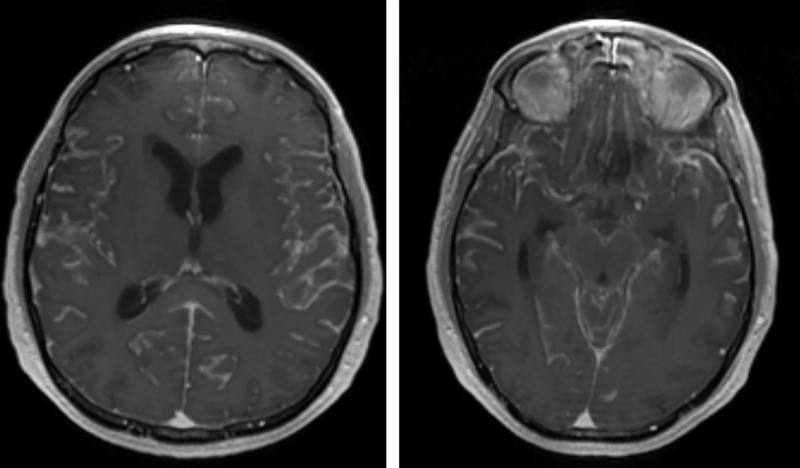

IRM - realce difuso de gadolinio - meningitis carcinomatosa